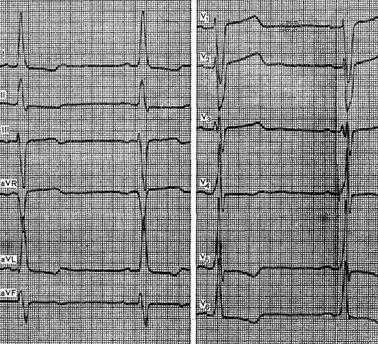

На рис. 42 представлена ЭКГ больного с гипертрофией ПП.

Рис. 42. ЭКГ при гипертрофии ПП. Высокий остроконечный зубец PII, III, aVF. В отведении VI зубец Р асимметричный с преобладанием положительной фазы.